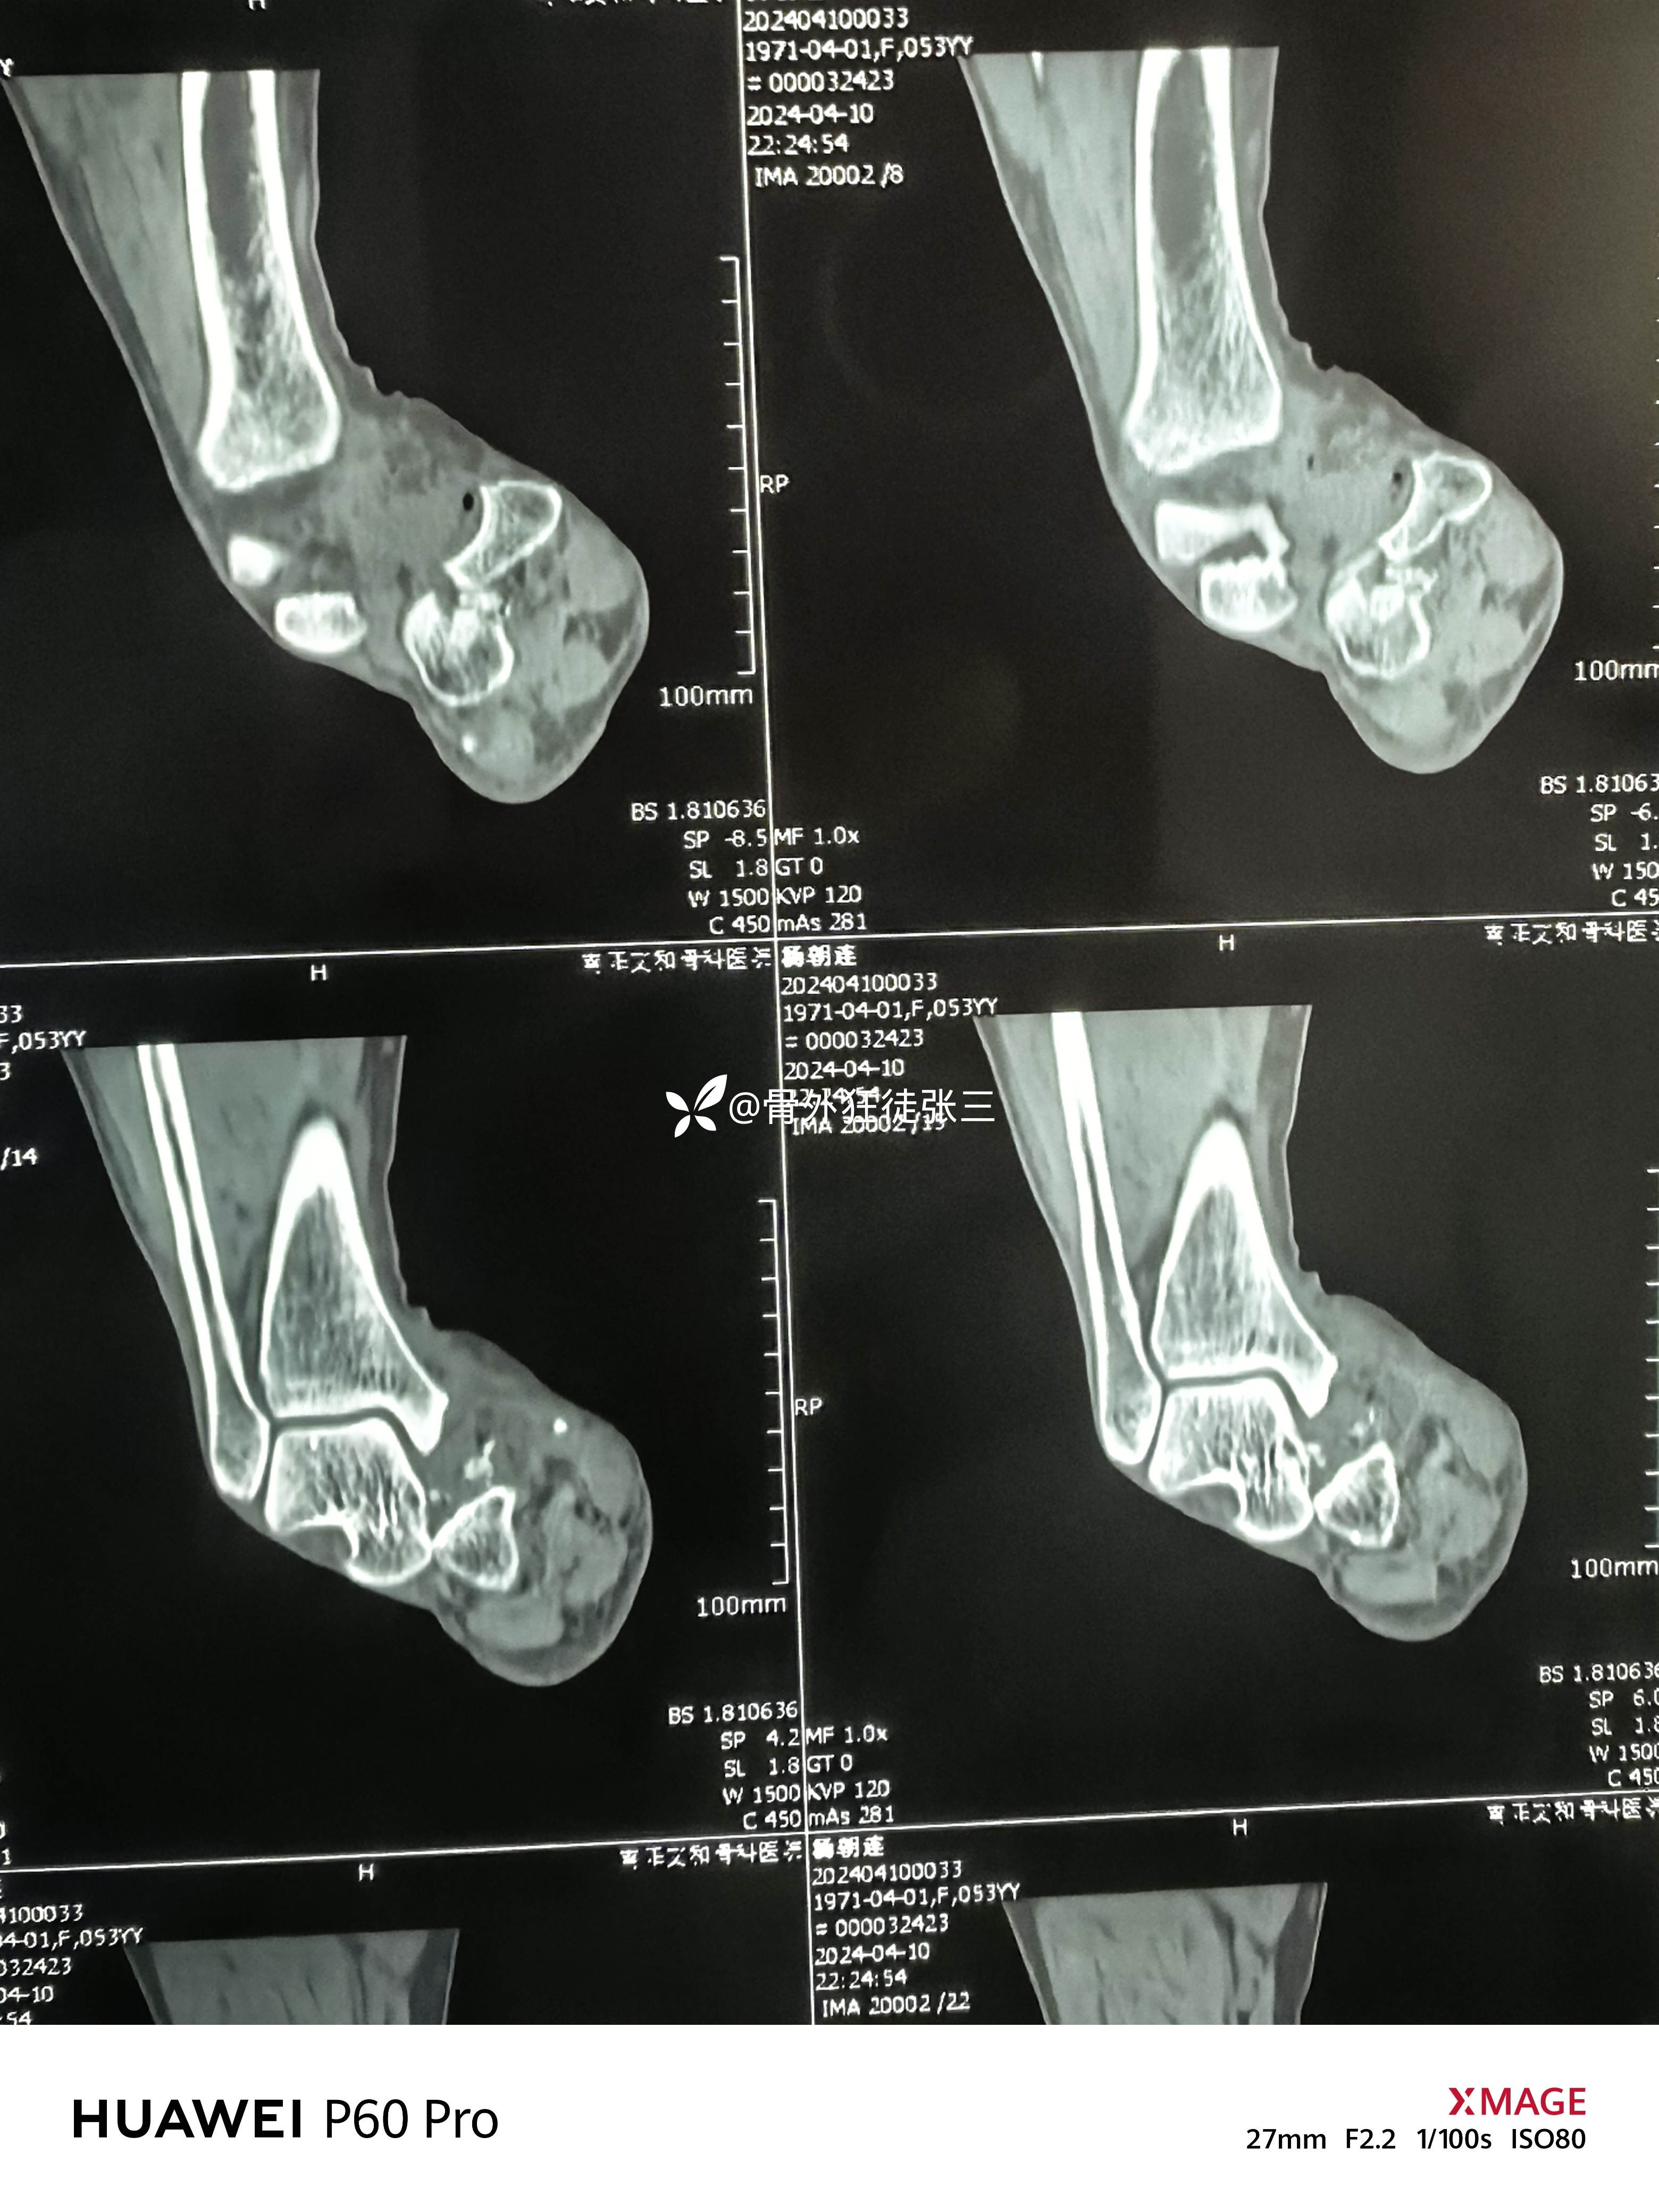

罕见损伤:距下关节脱位

主诉:车祸扭伤右踝关节致肿痛、畸形、活动受限1小时。

右踝关节肿胀明显,屈曲内翻畸形,活动受限。

右距下关节脱位(内侧型)